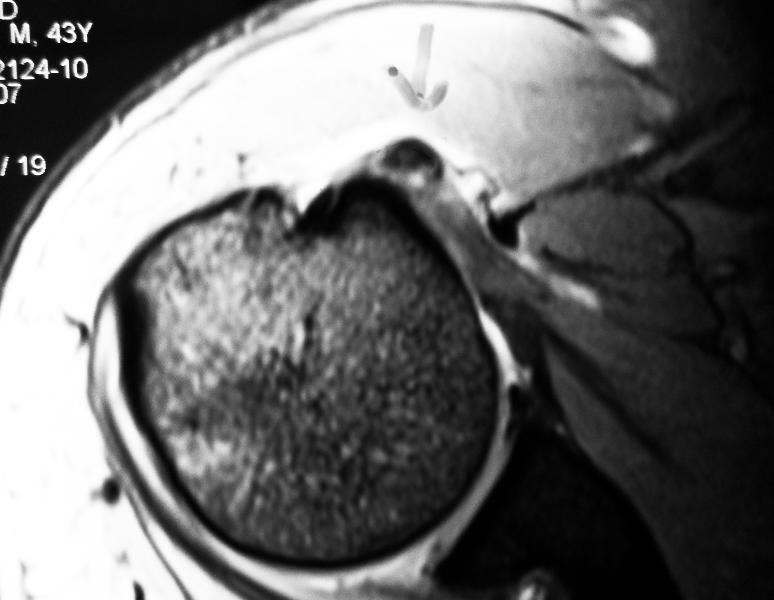

MRI scan when used to look for other problems in the shoulder, e.g. tendon tears, can also show the calcium deposits inside the tendons.

The treatment is to come to a correct diagnosis. I would do x-rays to look for spurs and calcium in the tendon. An MRI scan should be done to rule out any cuff tendon tear.